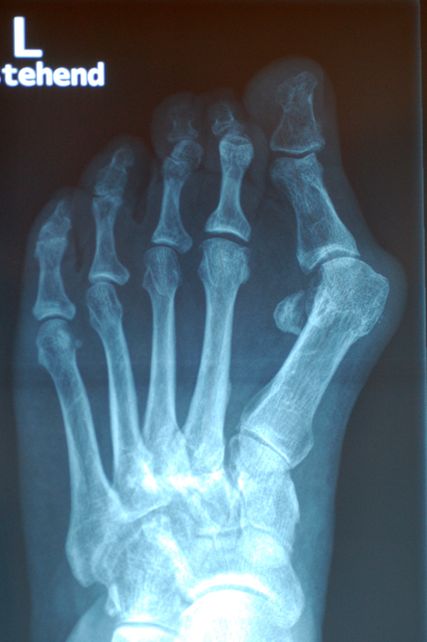

Abb. 1: Die Prominenz des Großzehenballens verstärkt sich erheblich aufgrund der M1-Pronation

Als komplexer pathologischer Prozess steht die M1-Pronation in engem Zusammenhang mit anderen Aspekten, nämlich dem HV-Winkel, dem Intermetatarsal(IM)-Winkel, einem abgeflachten Längsgewölbe und einer Hypermobilität. Eustace et al. zeigten 1994 einen signifikanten Zusammenhang zwischen der M1-Rotation und der Höhe des Längsgewölbes.7 Glasoe et al. vertreten ebenfalls die These, dass die Rotation des M1 von der Höhe des medialen Bogens abhängig ist.8 Sie konstatieren, dass bei abgeflachtem Längsgewölbe eine vermehrte Pronation im M1 stattfindet, bei erhöhtem mehr Supination. Mortier et al. beschreiben die typische Supination des M1 in der Allgemeinbevölkerung, wogegen bei HV-Deformitäten die typische Pronation des ersten Strahls zu beobachten ist.20 Dayton et al. fanden in ihrer Studie einheitlich pronierte M1-Positionen bei den untersuchten Füßen mit HV.4

Abb. 2: Die übermäßige Pronation des M1 verstärkt die im Röntgen deutlich sichtbare Lateralisierung der Sesambeine

Die Rolle des M1 besteht in Hinblick auf den Großzeh darin, dass eine übermäßige M1-Pronation ein Ungleichgewicht auf die Strukturen des Metatarsophalangeal-1-Gelenks bringt, die medialen Bänder überdehnt werden und das M1-Köpfchen nach medial gleitet (Abb.1). Die Position der Sesambeinchen lateralisiert sich. Entweder sie bleiben in ihren Gelenksflächen, gehalten von den medialen und lateralen metatarsophalangealen Ligamenten – Kim et al. nennen das „Pseudoluxation“ – oder sie subluxieren aus ihren Metatarsalköpfchenführungen.15 Dies ist die häufigere Variante (Abb.2).